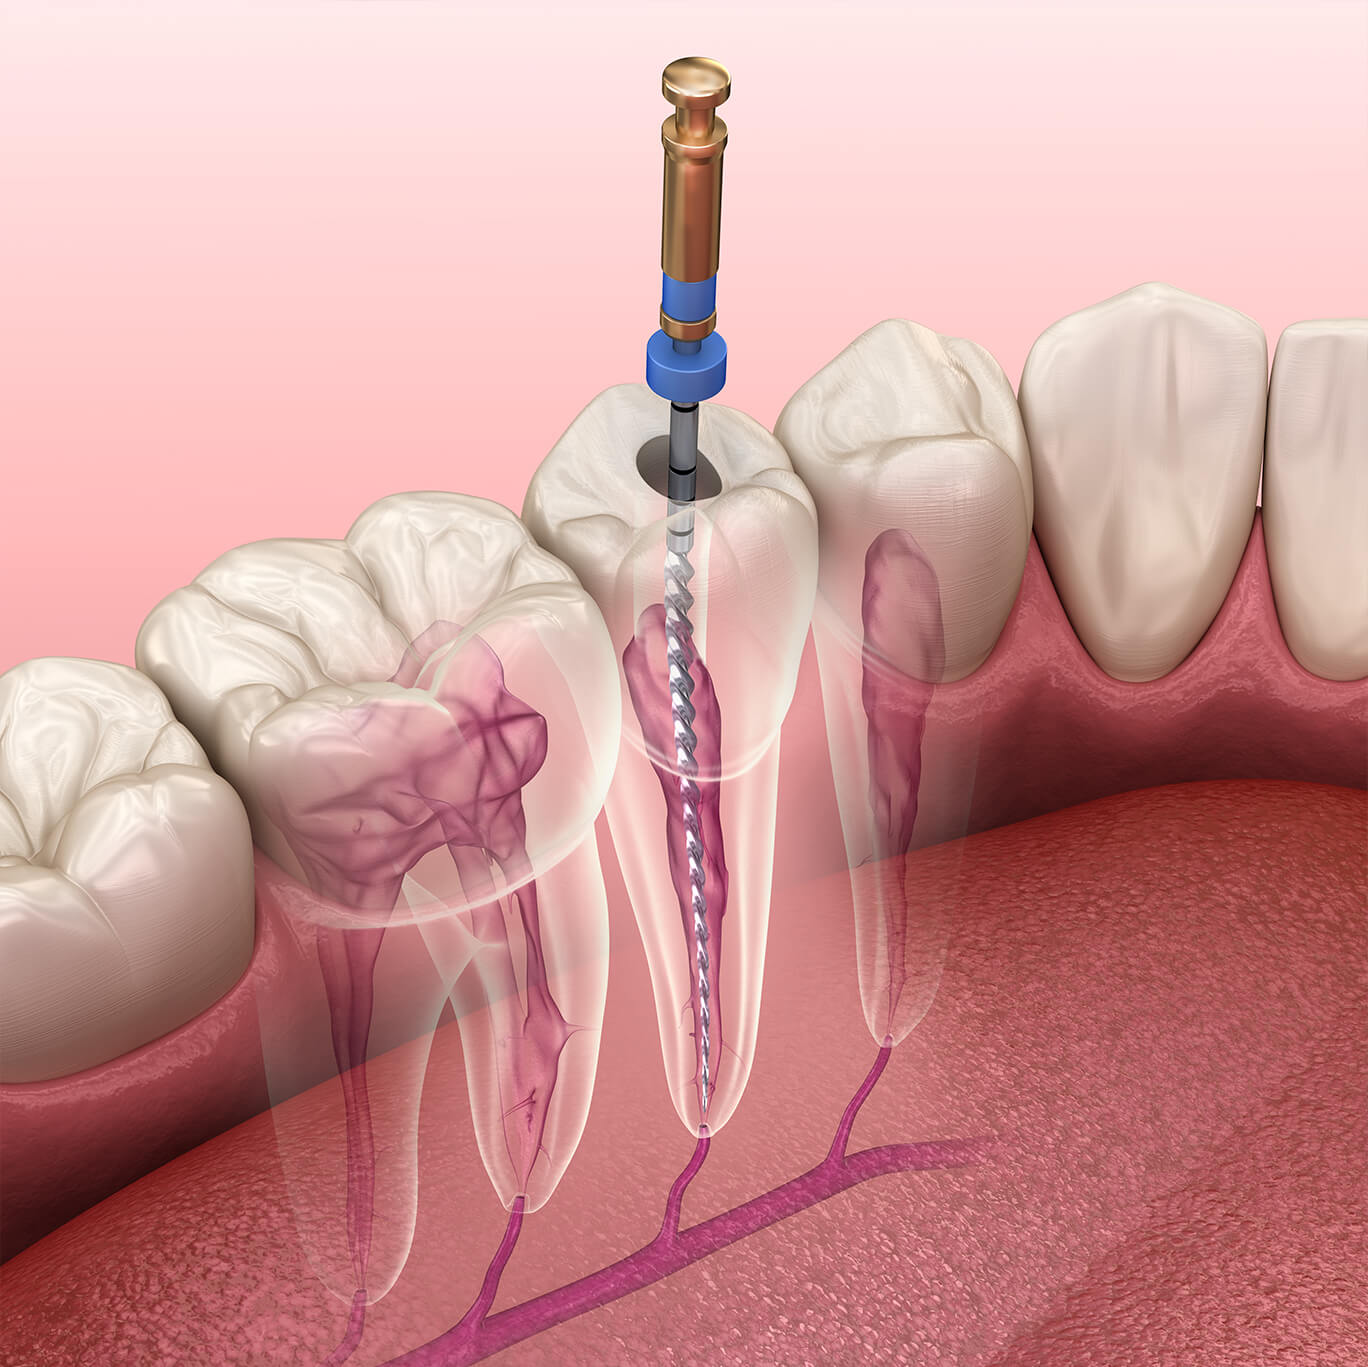

Endodontia / desvitalização

O profissional especializado nesta área faz a remoção da polpa (nervo) do interior da cavidade pulpar nos canais radiculares, seguindo para a sua substituição por material sólido, preocupando-se com o objetivo de manter o dente, conseguindo estabelecer as suas funções e evitar futuras complicações.

Este tratamento normalmente é realizado em 3 sessões: a primeira consiste em retirar a polpa (na raiz do dente) do interior da cavidade pulpar preparando assim os canais para a segunda sessão, na qual esta cavidade é preenchida com um material sólido (gutta), sendo que por fim é realizada a restauração final.

A Endodontia trata da estrutura interna de cada dente natural por meio de prevenção, diagnóstico e tratamento.

Os problemas que afetam a polpa dentária e os tecidos à volta da raiz do dente são a causa de muitas perdas de dentes e de dor. A Endodontia, conhecida também por desvitalização, é um tratamento para conservação do dente em boca.

A intervenção passa pela remoção da polpa do interior do dente, que é preenchido com um material biocompatível. Este material vai selar os canais dentários, numa tentativa de impedir a entrada de bactérias. Para o paciente é o modo mais eficiente de manter o dente e recuperar a função da boca.